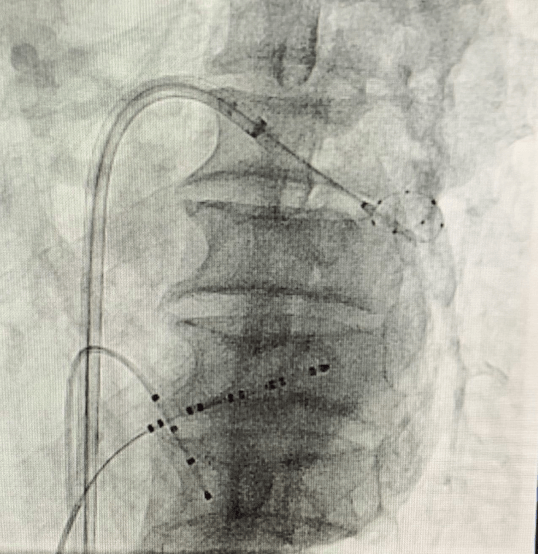

(手術(shù)過(guò)程)